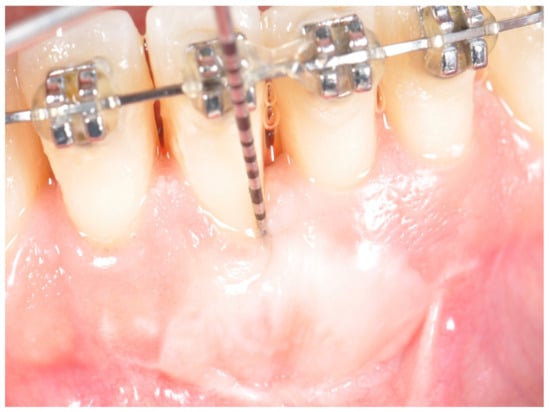

- The graft was measured with the probe and its measurements recorded;

- Palatal sutures and periodontal dressing were removed at one week; photographs and graft measurements were recorded.